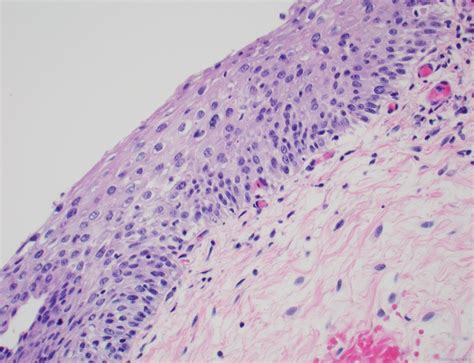

The term Low Grade Squamous Intraepithelial Lesion describes cells that look slightly abnormal under a microscope. These squamous cells line the outer surface of the cervix. When these cells are infected by certain strains of HPV, they may begin to change their shape or size. The “low-grade” designation indicates that the changes are mild and that the cells are not yet showing signs of becoming cancerous. In most cases, the body’s immune system is capable of clearing the HPV infection on its own, allowing the cervix to return to a normal, healthy state without the need for invasive medical procedures.

Medical professionals typically identify LSIL during routine cervical cancer screening procedures, such as a Pap test or a co-test that includes HPV testing. When a pathologist examines the cells collected during these tests, they look for specific cellular characteristics that indicate the presence of a lesion.